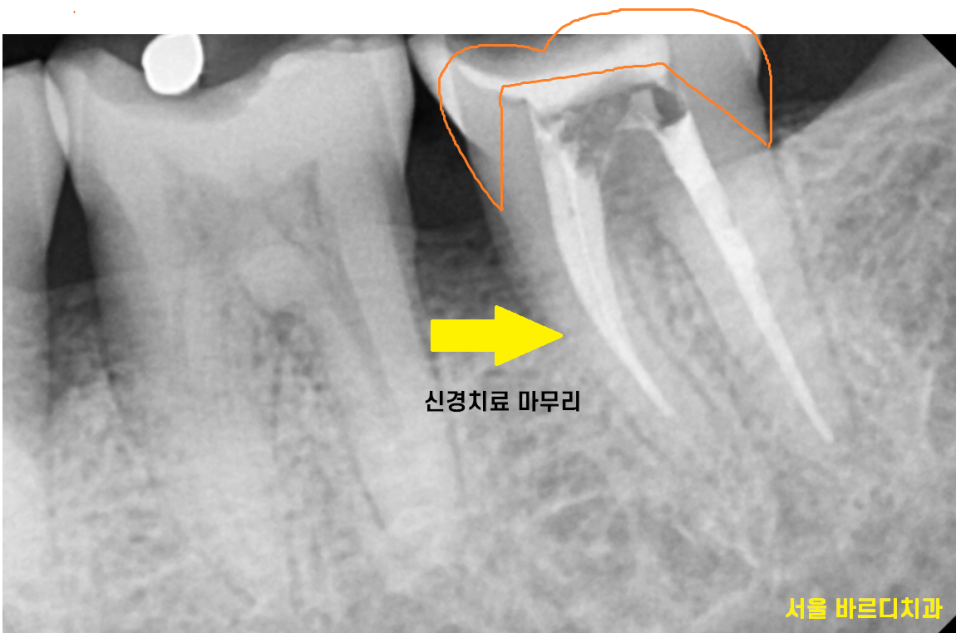

22.04.26

신경이 살아있기에

치아가 통증을 느끼는 거라서

많이 파인 치아를 망월동 치과에서

신경치료 하였습니다.

22.05.11

신경치료의 마무리는

보철을 씌우는 것으로 마무리됩니다.

신경을 제거하고나면

내부가 텅 비게 되는데

한마디로 텅빈 강정이 되어버립니다.

치아는 신경을 통해

영양분을 공급받는데

신경치료를 받게되면

신경을 제거하면서

영양공급이 끊겨버리기 때문이죠~!